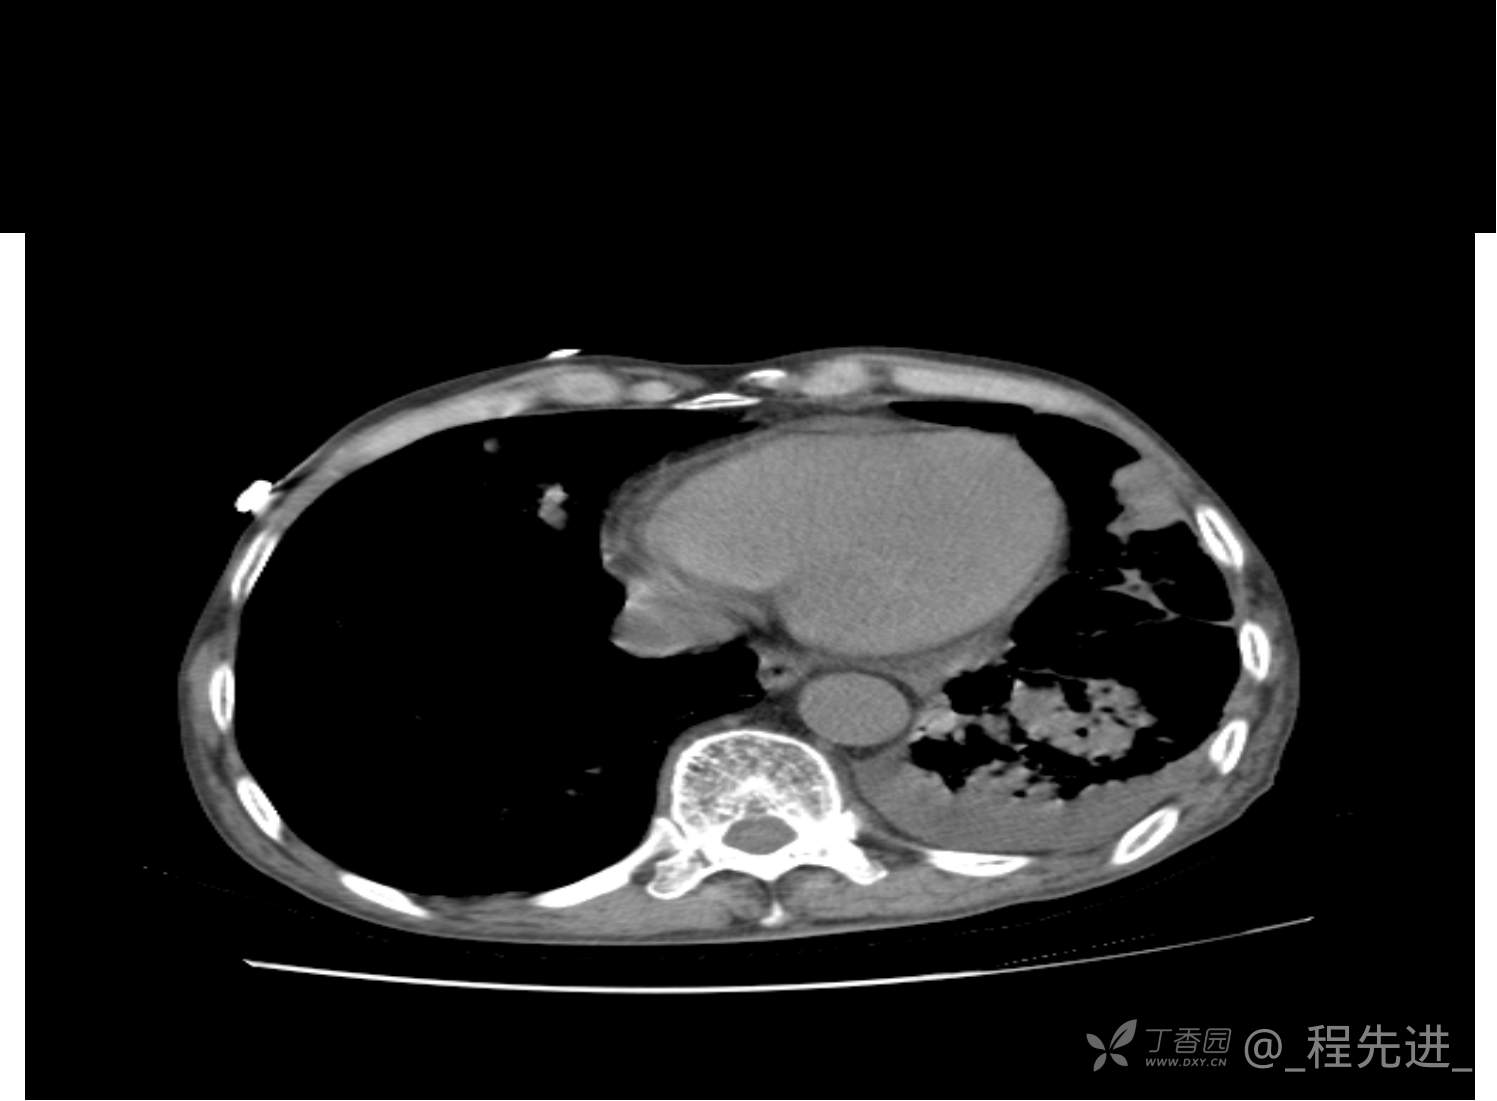

患者性别:男

患者年龄:81岁

简要病史:反复咳嗽、咳痰20余年,加重1周。两肺呼吸音低,可闻及散在干湿啰音。